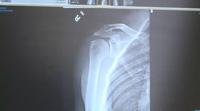

Dr. Christensen points out on Stephanie Spear's x-rays, she has arthritis making her an ideal candidate for a different type of shoulder replacement called a reverse shoulder replacement.